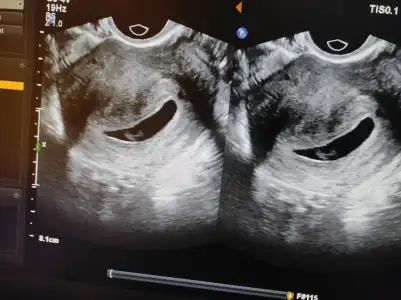

Kızlar az önce doktor kontrolünden çıktım. Daha önce boş gebelik geçiren biri olarak bu defa kesenin içinde bebeği görünce gözyailarımı tutamadm kalp atışını da dinledim. Karından bakılan ultrasonla görünmedi doktor alttan bakabilirim dedi kabul ettim. Çünkü 1-2 hafta daha bekleyerek strese girip hem bebeğe hem kendime zarar verecektim. Bir de önceki tecrübemden hareketle 9.haftaya kadar alttan ultrasonla bebek oluşacak mı yolk sac oluşacak mı diye o kadar çok kurcaladılar muayene ettiler ki artık ben de bi aşinalık oldu ister istemez ayrıca hiçbir kanama vs de olmamıştı kürtajla almışlardı boş keseyi. Neyse eğer alttan muayeneden korkanlar varsa diye biraz detaylandırdım. Sonuç olarak bu defa her şey yolunda ilerliyor. Sat 30 ocak 6+6 ama doktor bebek için 6+2 gelişimi dedi hiçbir sıkıntı yok dedi kan ve idrar tahlillerin temiz çıktı dedi. Cinsel ilişkiyi sordm bir sıkıntı yok ama kanama alanı oluşturabilir dedi öyle bir şey olursa hemen gel dedi. 1 ay sonra kontrole çağırdı. Durumlar böyle 🧿🙏🙂

• IMG_20240318_100846.webp

IMG_20240318_100846.webp

42,8 KB · Görüntüleme: 64